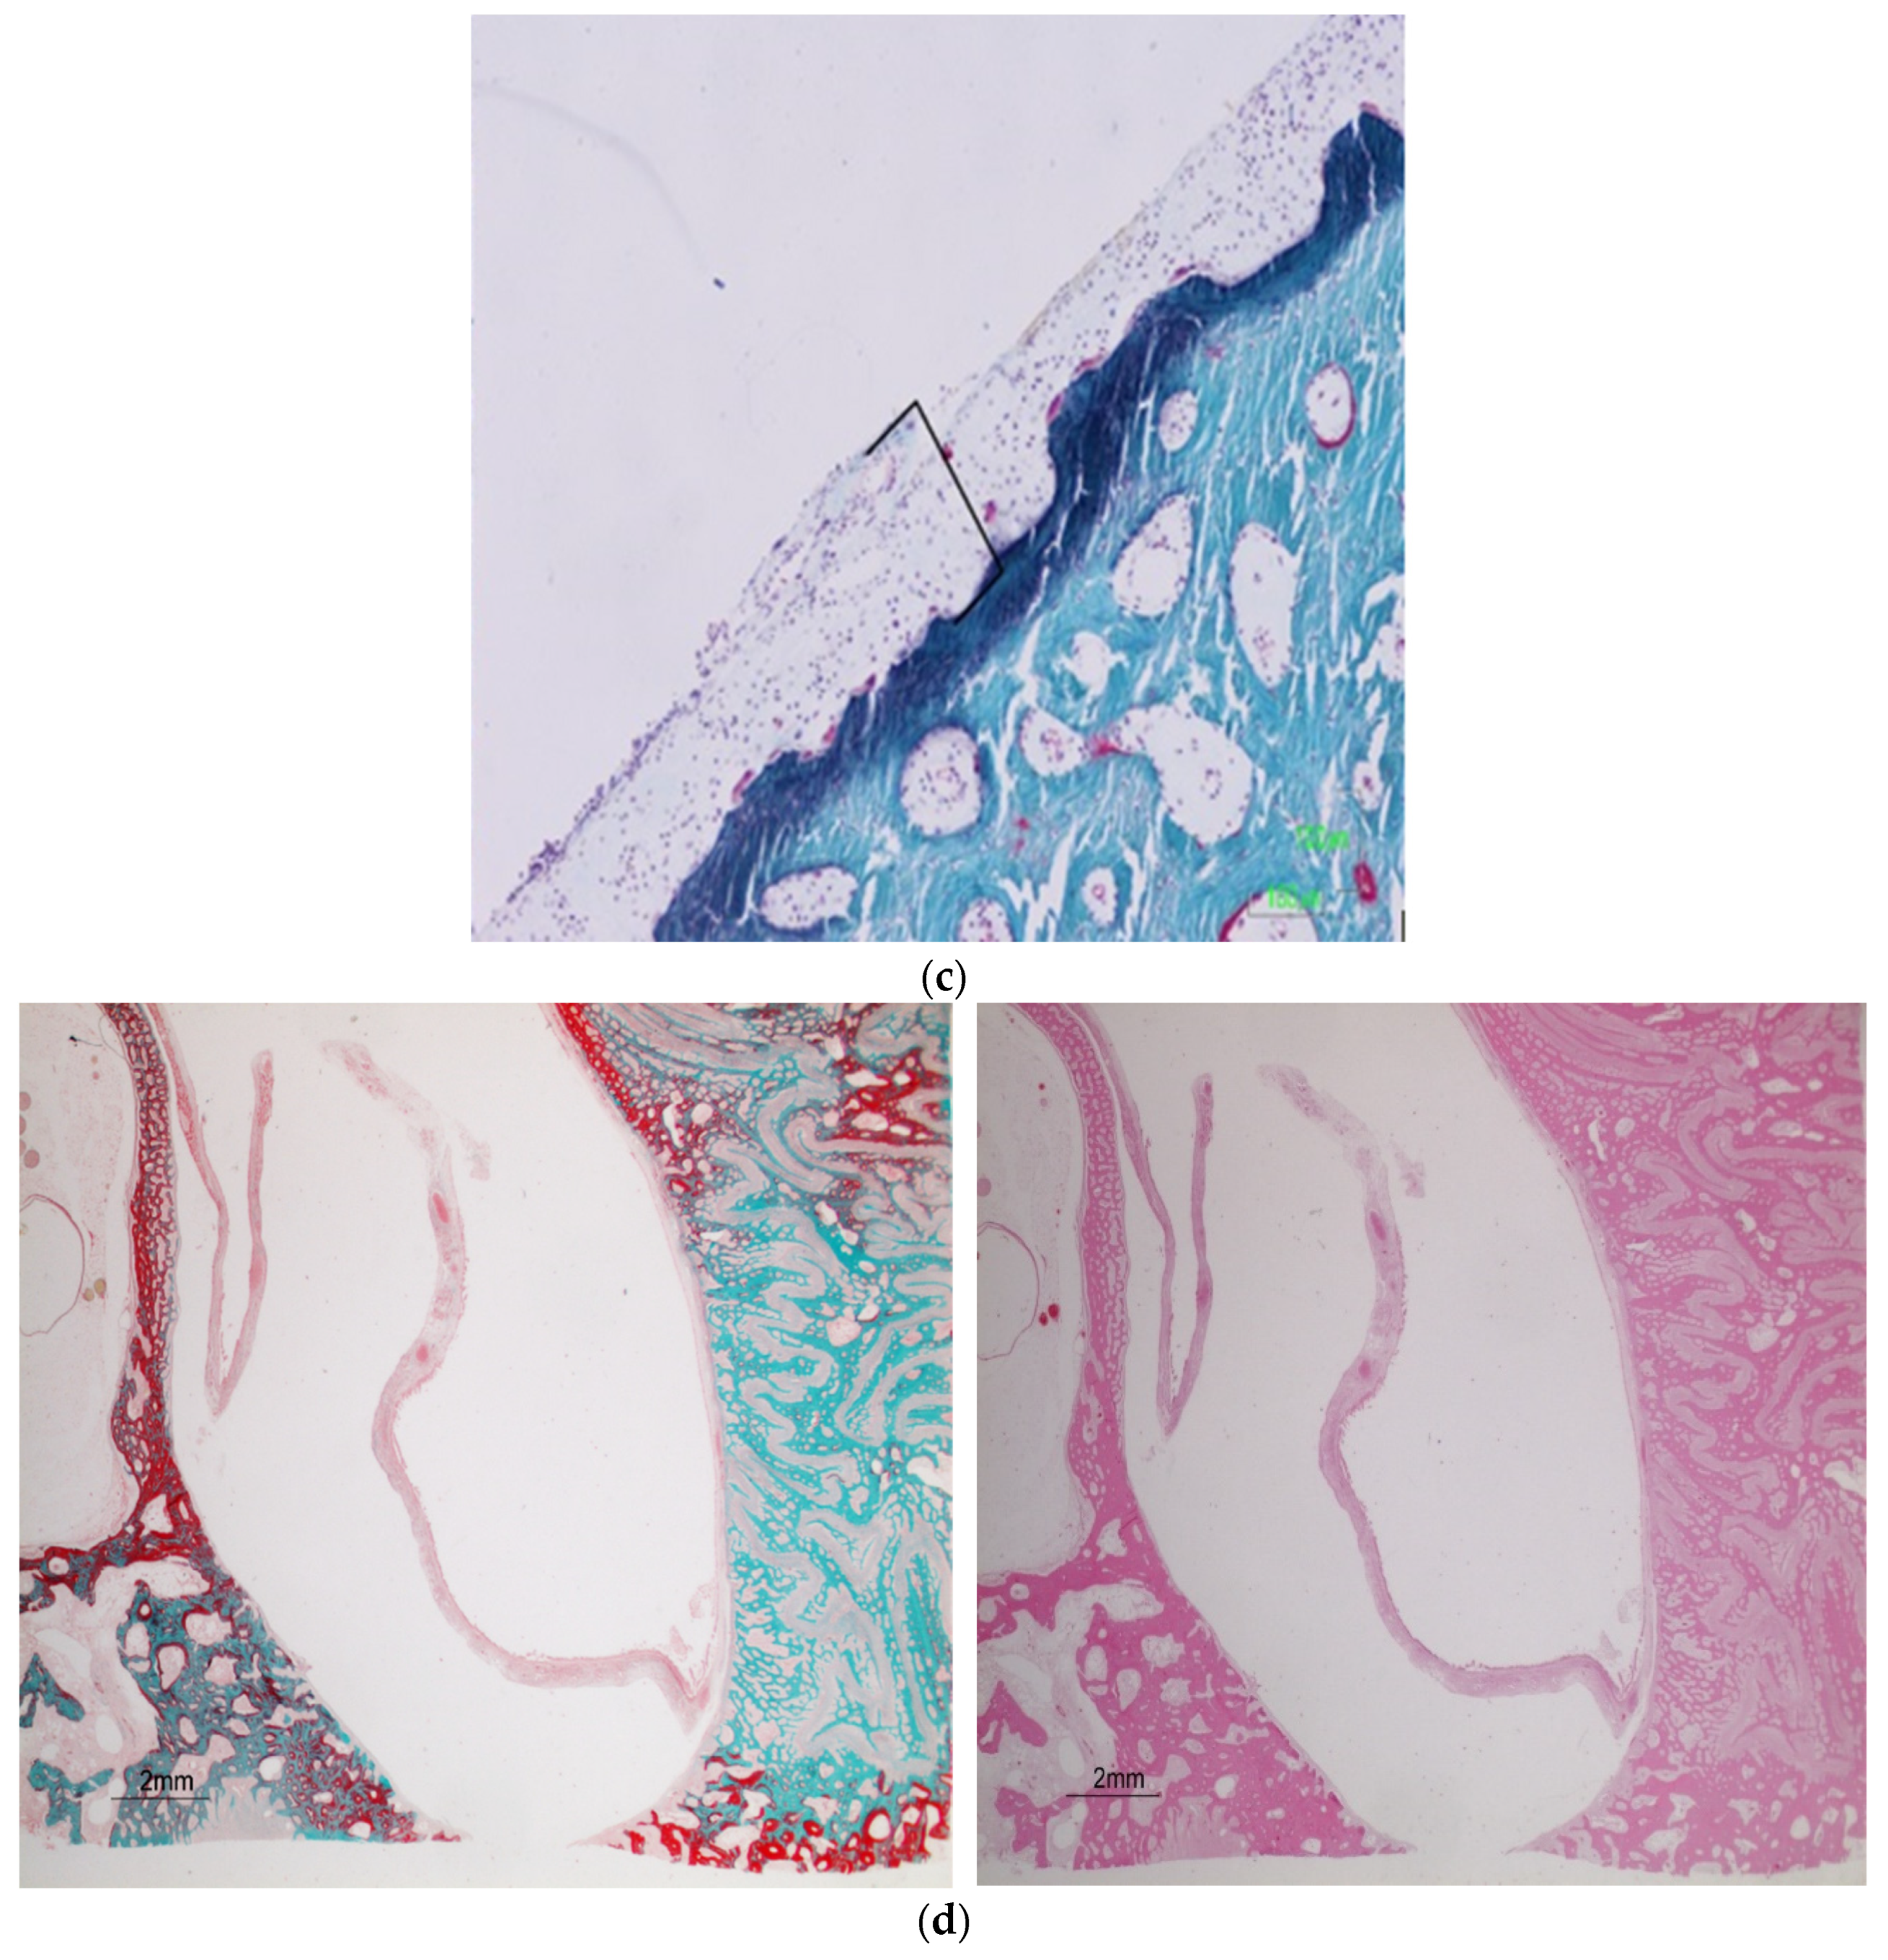

| 11 | 9.6 | no | yes | yes |

| 18 | 9.6 | no | yes | no |